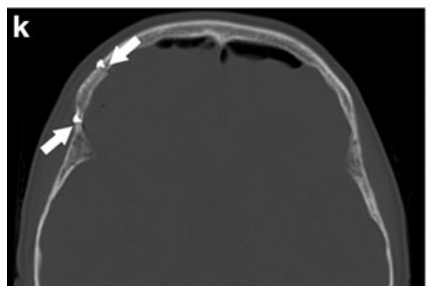

k 术后CT:示骨窗范围(箭头所示)